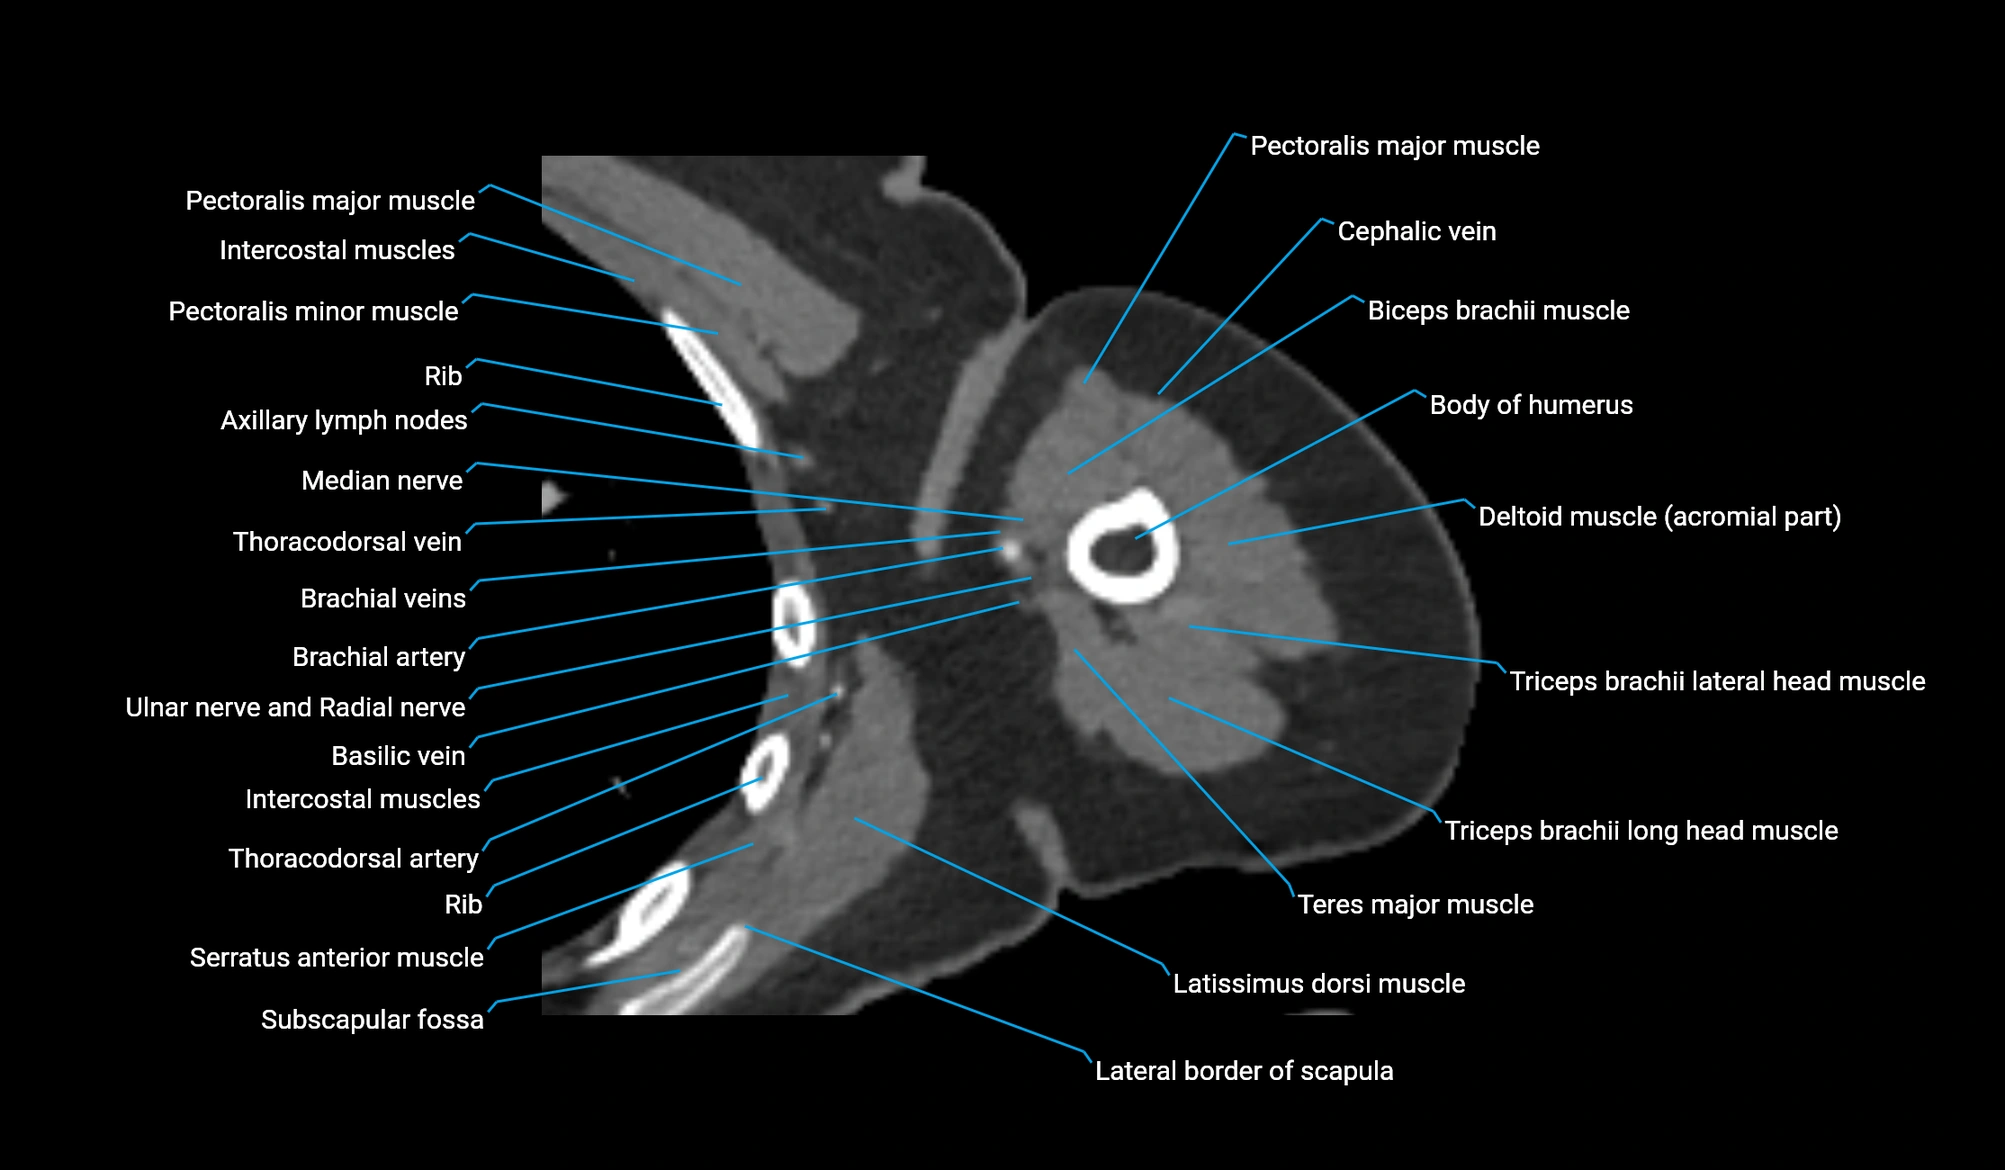

- Axillary lymph nodes

- Basilic vein

- Biceps brachii muscle

- Body of humerus

- Brachial artery

- Cephalic vein

- Clavicular part of deltoid muscle

- Coracobrachialis muscle

- Lateral border of scapula

- Lateral head of triceps brachii muscle

- Long head of triceps brachii muscle

- Medial head of triceps brachii muscle

- Median nerve

- Pectoralis major muscle

- Pectoralis minor muscle

- Subscapular fossa

- Teres major muscle

- Thoracodorsal artery

- Triceps brachii muscle